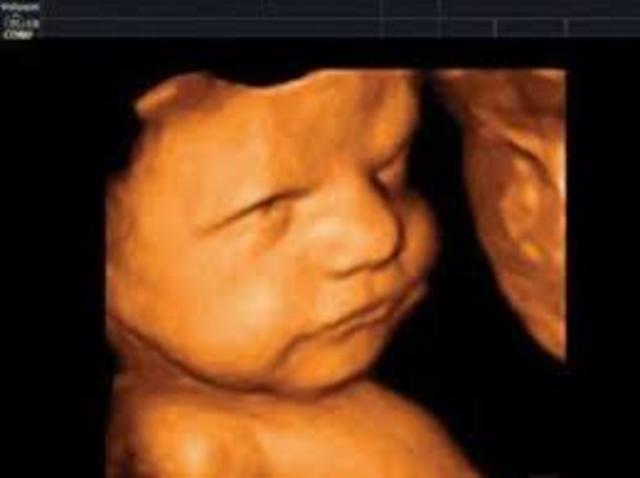

• Semana 20

Semana 20

El lanugo cubre todo el cuerpo

Aparecen las cejas y las pestañas

Aparecen las uñas en pies y manos

El feto es más activo con mayor desarrollo muscular

La mujer puede sentir al feto moviéndose

Los latidos cardíacos fetales se pueden escuchar

• Semana 24

Semana 24

Las cejas y las pestañas están bien formadas

Todas las partes del ojo están desarrolladas

El feto presenta el reflejo prensil y de sobresalto

Se comienzan a formar las huellas de la piel plantar y de la piel palmar

Se forman los alvéolos pulmonares